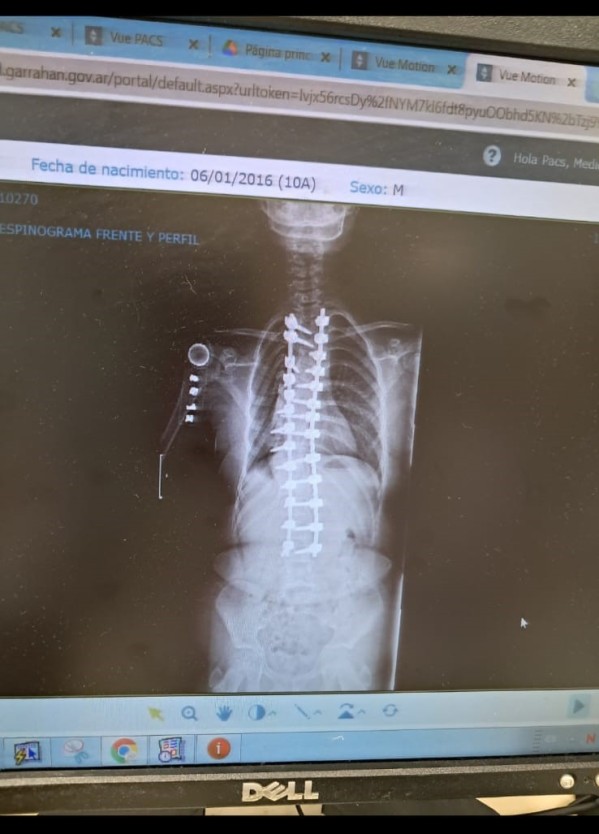

Este miércoles 4 de marzo no fue un día cualquiera para la familia Ferreira. Johana, la niña que conmovió a General Rodríguez con su lucha, volvió a cruzar las puertas de la Escuela Primaria Nº14 para comenzar el 5º grado. El camino no fue sencillo: Johana, quien cumplió 10 años el pasado 6 de enero, debió enfrentar una escoliosis espinal congénita (foto) detectada al nacer que, con el tiempo, convirtió acciones simples como caminar o atarse los cordones en un suplicio.

La operación, realizada en el Hospital Garrahan, marcó un antes y un después. Tras meses de utilizar un "halo" en su cabeza y una preparación rigurosa, la cirugía fue un éxito. "Desde que se operó hasta ahora no siente dolor; los médicos del Garrahan son los mejores", asegura su madre con alivio. El próximo 21 de abril se cumplirá un año de aquella intervención que le cambió la vida.